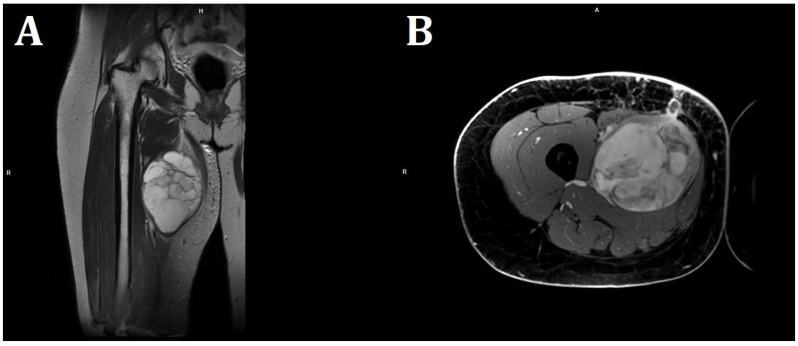

Case presentation: We report the case of a 36-year-old female patient on the 11th day of the puerperium after a cesarean section. The patient presented to the gynecology ward owing to the sudden appearance of a tumor in the medial part of her right thigh. The lesion was non-painful, mobile, soft, approximately 20 cm in diameter, and protruded above the level of the rest of the thigh surface. A suspicion of hematoma was raised. The final diagnosis was high-grade MLPS.